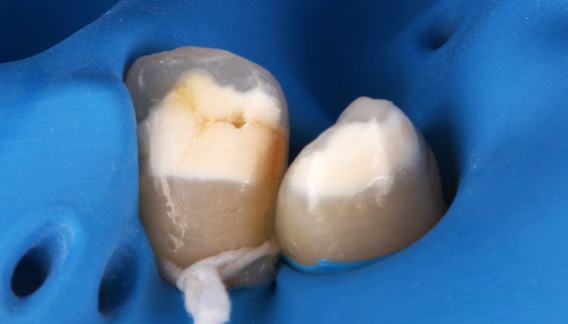

| 院長コメント | ①むし歯を治療して歯を型どりする時 ②ジルコニアを歯と接着させる時 唾液を極力排除する必要があります。ラバーダムというゴムの膜を用いて歯を唾液から隔離します。今回はかぶせ物(クラウン)の形で接着面全周をラバーダムの上に出すのはかなり難しかったのですが、工夫をすることで接着面全てをラバーダムの上に設置することができ、接着力を最大限に発揮できました。 |